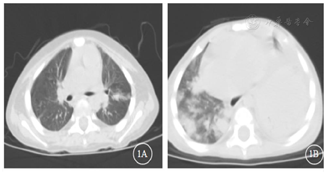

入院后实验室检查:血常规+C反应蛋白(表1),降钙素原0.138 ng/ml。巨细胞病毒(cytomegalovirus,CMV)DNA和EB病毒DNA(EBV-DNA):阴性。真菌D-葡聚糖(G)和曲霉菌半乳甘露聚糖(GM):阴性。血培养:无细菌生长。肝功能:谷丙转氨酶249.9 U/L,谷草转氨酶92.9 U/L,碱性磷酸酶472.3 U/L,γ-谷氨酰转肽酶1135.4 U/L。肾功能、电解质正常。淋巴细胞亚群:T淋巴细胞(CD3+)96%,T8淋巴细胞(CD3+CD8+)92%,T4淋巴细胞(CD3+CD4+)4%,CD4/CD8 0.05,NK细胞(CD16+56+)4%,B细胞(CD19+)0%。胸部CT:肺部团片影(图1A)。积极完善纤维支气管镜检查,肺泡灌洗液革兰染色:检出阴性杆菌、未检出抗酸杆菌。肺泡灌洗液培养阴性、未检出嗜血杆菌。肺泡灌洗液真菌培养基鉴定:未检出真菌。肺泡灌洗液下呼吸道多重细菌核酸检测:肺炎链球菌DNA、金黄色葡萄球菌DNA、耐甲氧西林mecA基因、大肠埃希菌DNA、肺炎克雷伯菌DNA、铜绿假单胞菌DNA、鲍曼不动杆菌DNA、嗜麦芽窄食单胞菌DNA、流感嗜血杆菌DNA、嗜肺军团菌DNA、结核分枝杆菌复合群DNA、肺炎支原体DNA、肺炎衣原体DNA均阴性。肺泡灌洗液宏基因组检测(metagenomics next generation sequencing,mNGS):奴卡菌属;血mNGS:奴卡菌属;PICC管培养:奴卡菌属。胸部CT示肺部片影持续进展,左肺实变伴胸腔积液出现(图1B),右侧第五脚趾呈现黑色(图2A)。影像学CT提示肝脏脓肿(图3A),双侧大脑半球多发团片状异常密度影(图3B)。右侧第五脚趾组织病理培养、骨髓培养、血培养、脑脊液和复查血液mNGS均检出小克银汉霉(图2B~D)。治疗期间血象持续、进行性下降,呈严重骨髓抑制血象(表1)。2021年7月14日行骨穿:骨髓形态增生活跃,粒红系比值形态正常,巨核细胞50个,MRD<0.01%,MLL-AF1P基因阴性,STR示完全供者嵌合状态(姐姐来源细胞占100%)。2021年8月6日复查骨髓形态示增生重度减低,红系两系受抑制,全片未见巨核细胞,MRD<0.01%,MLL-AF1P基因阴性。2021年8月6日行脑脊液检查:脑脊液细胞数为3×106/L,生化正常,体液细胞学未见异常细胞,白血病免疫分型未见异常表型细胞。

入院后给予舒普深50 mg/kg、每8小时1次和卡泊芬净首剂70 mg/m2、维持剂量50 mg/m2抗感染、他克莫司0.5 mg、每12小时1次和甲泼尼龙片6 mg、每日1次抗排异治疗,患儿体温稳定。2021年6月26日复查胸部CT提示肺炎加重,停卡泊芬净,改为伏立康唑8 mg/kg、每12小时1次抗真菌治疗。2021年7月3日患儿再次出现反复发热,以低热为主,热峰37.7~38.0℃,复查胸部CT示仍进行性加重。2021年7月7日完善纤维支气镜检查,肺泡灌洗液mNGS提示皮疽奴卡菌属,给予调整为美罗培南40 mg/kg、每8小时1次,利奈唑胺10 mg/kg、每8小时1次,继续联合伏立康唑抗感染治疗,并间断输注静注人免疫球蛋白2.5 g免疫支持治疗,患儿仍有低热。2021年7月12日PICC管培养和血mNGS回示见奴卡菌属生长,联合复方磺胺注射液0.2 g、每12小时1次联合抗感染治疗,但发热热峰呈升高趋势,38.5℃,每日1~2次,且三系出现进行性下降,给予粒细胞刺激因子升白细胞、输注悬浮红细胞和机采血小板支持治疗,并停用影响血象的药物。2021年7月17日停斯沃,加用替加环素1.2 mg/kg、每12小时1次,患儿体温热峰仍持续升高,达39.0℃,热峰2~3次/d。2021年7月23日停替加环素和美平,改为头孢他啶阿维巴坦62.5 mg/kg、每8小时1次,阿米卡星7.5 mg/kg、每12小时1次抗感染治疗,并予甲强龙改为静点控制炎症反应,停用他克莫司,患儿体温仍无好转,甲强龙逐步减量。2021年7月24日出现右侧第五脚趾指甲发黑,面积逐渐扩大至甲床、指腹(图2A)。2021年7月27日行右侧第五脚趾指甲组织培养。2021年7月29日培养结果回示小克银汉霉,给予停用威凡,加用两性霉素B脂质体3 mg/kg、每日1次,患儿每日仍有2~3次热峰,热峰稍有下降,38.0℃,应用两性霉素B脂质体后患儿出现顽固性低钾血症。2021年8月2日更换为两性霉素B胆固醇硫酸酯复合物4 mg/kg、每日1次抗真菌治疗,患儿热峰和发热间隔无好转。